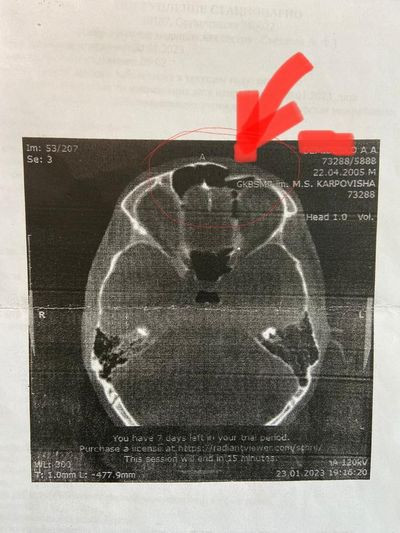

Об этом случае рассказали врачи Красноярской межрайонной детской больницы №4. Мальчик бежал к автобусу, поскользнулся, упал и ударился лбом о тупой ограничитель на тротуаре. Ребёнка сперва доставили в БСМП, где его осмотрел нейрохирург. По результатам компьютерной томографии был выявлен вдавленный перелом передней стенки левой лобной пазухи с попаданием обломков в её полость.